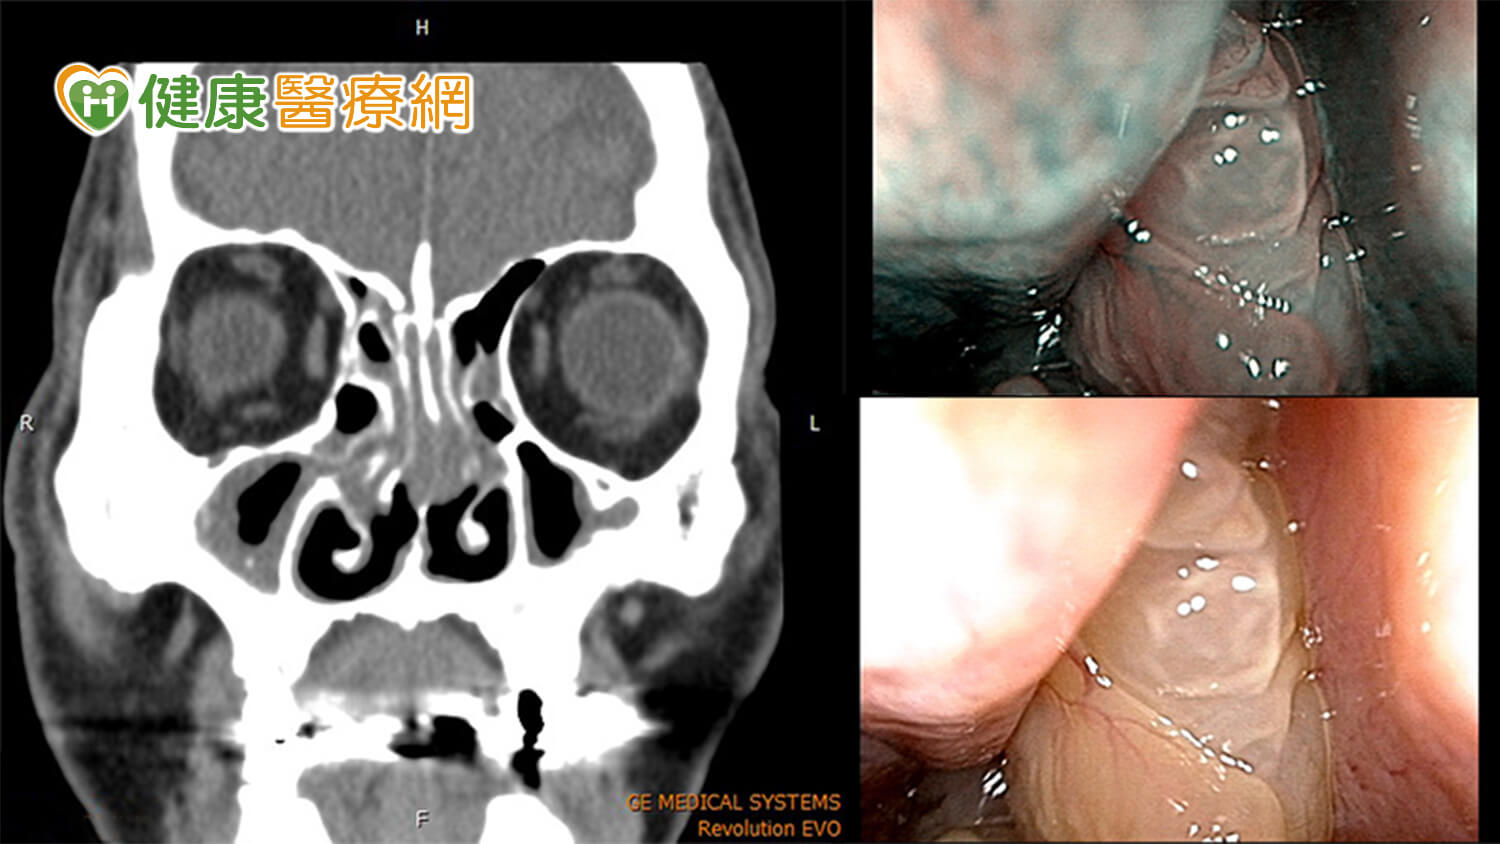

桃園一名 45 歲張先生,長期飽受鼻塞困擾,不僅影響白天精神,夜間甚至需要張口呼吸才能入睡,嚴重影響生活品質。為尋求進一步治療,他特地北上至雙和醫院耳鼻喉科就診,由巫承融醫師進行內視鏡檢查。

檢查發現,張先生右側鼻腔後段遭肥大鼻息肉阻塞,氣流無法順利通過,同時合併鼻中隔彎曲 + 雙側下鼻甲肥厚,導致雙側鼻道皆出現明顯阻塞。經巫醫師詳細評估與溝通後,決定接受單側功能性鼻竇內視鏡手術,合併雙側微創鼻中隔鼻道成型手術。